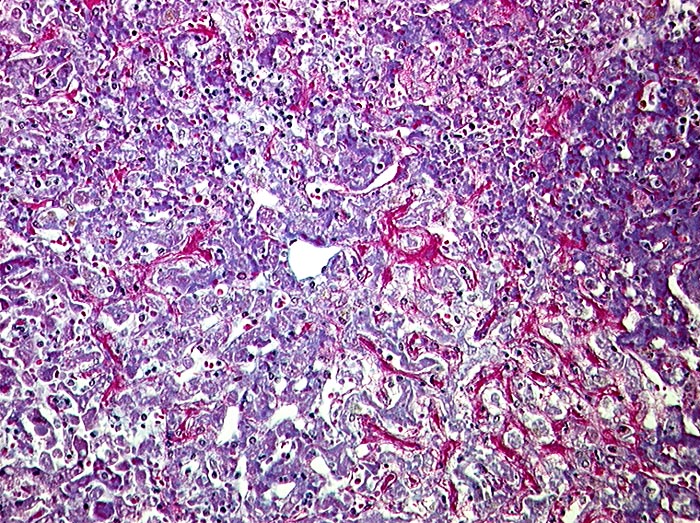

Subakute Stauung

vaskulär / Durchblutungsstörung

Leber

Znetralvene in der Mitte des Bildes. Die perivenulären Sinusoide sind prall gefüllt mit Blut. Die Leberzellbalken sind leicht verdünnt (druckatroph). Keine Fibrose.